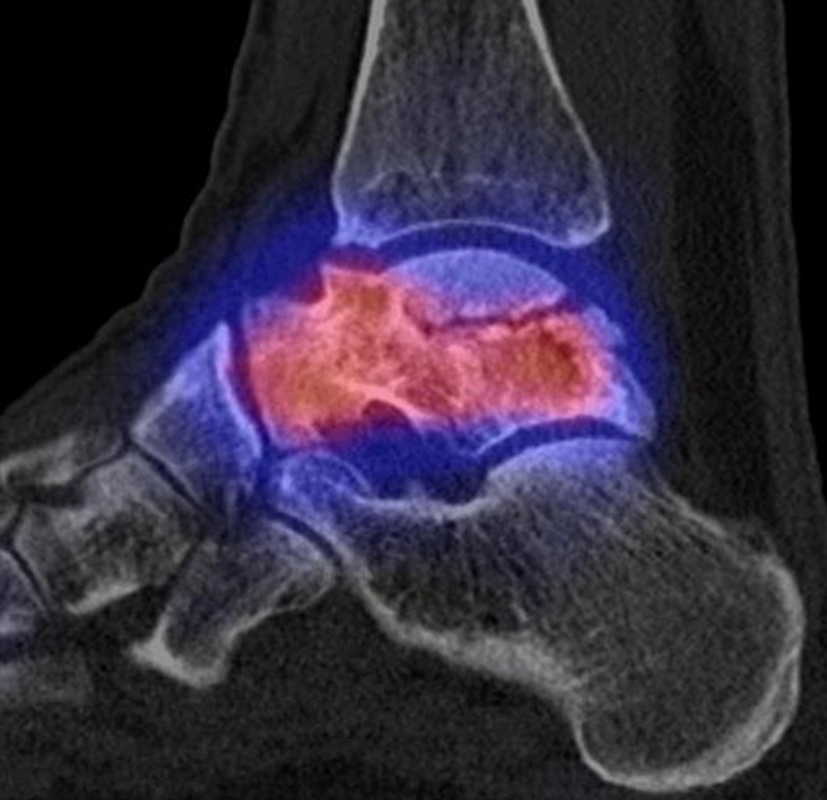

Abbildung 9.2.a bis d: SPECT/CT zur Beurteilung der Knochen-Vitalität bei einer Talusnekrose. 5 Jahre zuvor während der Arbeit war die Patientin beim Treppensteigen umgeknickt und zog sich Außenbandrupturen zu. Nachfolgend persistierende Beschwerden mit Entwicklung einer Talusnekrose. Frage nach Vitalität und Ausdehnung der Nekrose. Deutliche bis intensive Traceranreicherung im Bereich des linken Talus. Im SPECT/CT befindet sich der Hypermetabolismus in allen Abschnitten des Talus mit relativer Aussparung eines sich demarkierenden Fragmentes lateral, was die laterale Talusschulter umfasst, die Größe beträgt transversal ca. 23 x 16 mm. In diesem Fragment relativ homogene Skelettstruktur, diese Befunde weisen auf eine trophische bzw. nekrotische Störung des Talus hin mit einem sich demarkierendem Fragment, welches die laterale Talusschulter beinhaltet.

Die Abbildung 9.3.a bis d zeigt ein weiteren Fall mit einer SPECT/CT zur Beurteilung der Knochen-Vitalität bei einer Talusnekrose. Die Bilder zeigen eine abgelaufene Nekrose mit zystischen Resorptionen des linken Talusdoms bei nachweislich erhaltener Vitalität der umgebenden Knochenabschnitte aufgrund des hier überall deutlich erhöhten Knochenmetabolismus (= inkomplette Restitutio). Aufgrund der nachweislich erhaltenen Vitalität konnte erfolgreich eine Knochen-Transplantation erfolgen.Deutlich geringer ausgeprägte nekrotische Veränderungen auch im rechten Talusdom bei hier weitgehend erhaltenen Gelenkkonturen.